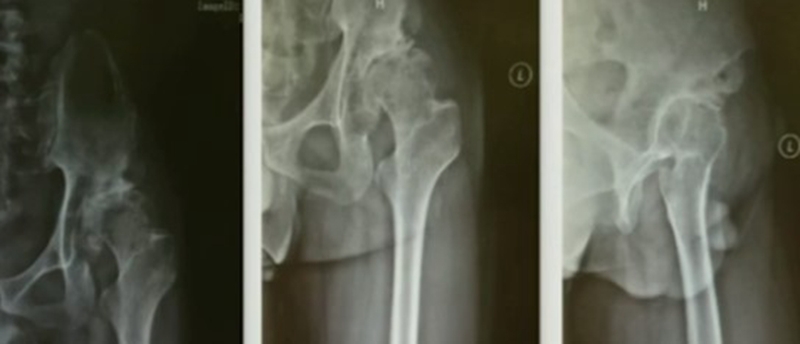

Ⅰ、大粗隆畸形

(1)悬突型:大粗隆过度增生或移位,偏向内侧或前后方。

阻挡髓腔开口,内外旋时,大粗隆边缘与髋臼发生撞击;根据髓腔延长线开口,去除大粗隆多余骨质,去除大粗隆前后方骨赘,避免骨性撞击。

(2)高骑跨型:大粗隆位置高耸

大粗隆尖与髋臼边缘撞击,如果在肢体等长情况下,撞击仍无法避免,需要考虑大粗隆滑移截骨。

Ⅱ、股骨颈畸形---髋内外翻,offset异常

(1)颈干角偏小(<120°)——髋内翻

髋内翻,颈干角小,偏心距较大,选择high-Offset假体,以维持外展肌张力。

(2)颈干角过大(>140°) ——髋外翻

髋外翻多见于DDH,难度在于股骨距内侧皮质阻挡假体完全坐入髓腔,强行打击造成股骨距骨折。